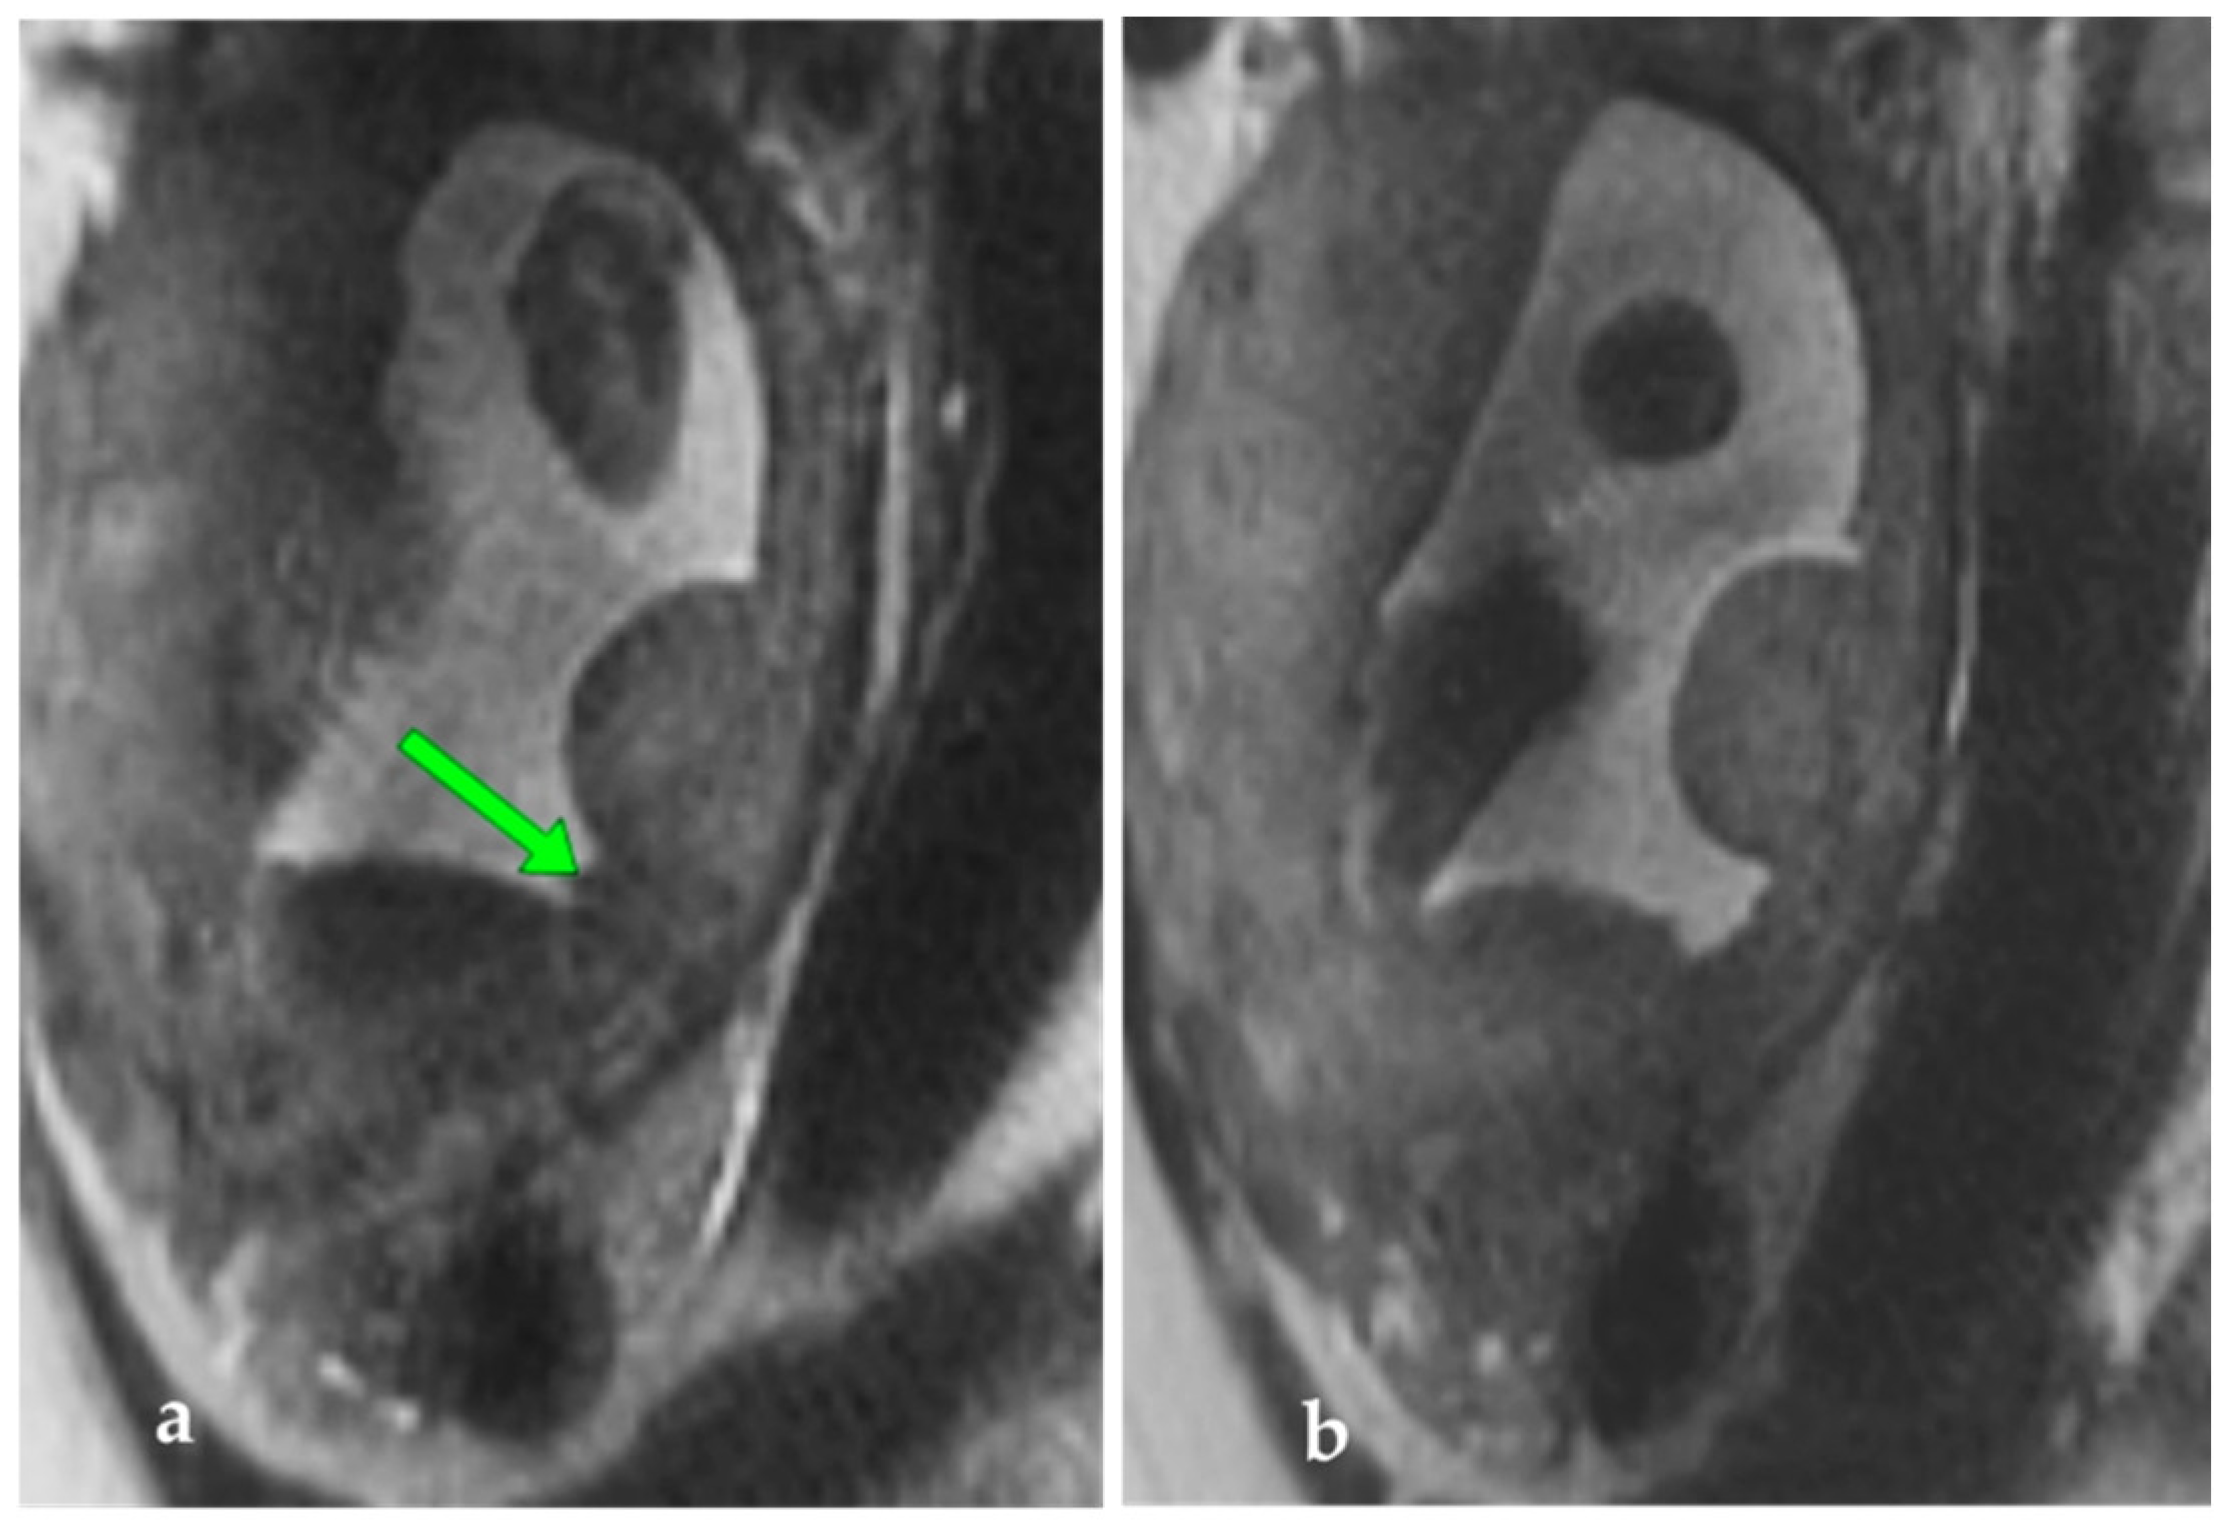

To rule out the presence of other placental satellites and to clarify the relationship between the umbilical vessels and the lobe, MRI was performed at 28 WG. MRI examination confirmed the presence of the abnormal placental lobe measuring 36.5/19/35 mm, connected by a narrow band of tissue to the rest of the placental parenchyma, possibly placental vessels (Figure 2). The diagnosis of succenturiate placenta was thus confirmed, without other placental abnormalities, and a normal insertion of the umbilical cord.

Figure 2. (a,b). MRI, Serial sagittal T2 sections at the level of the uterus. Arrow – band of placental parenchyma between the placenta and the accessory lobe.